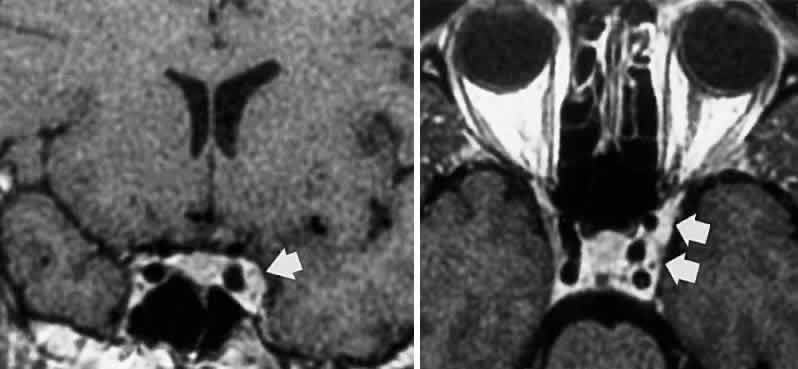

Primary neurinoma of the oculomotor nerve is a relatively rare lesion that should be considered in children or young adults with insidious third nerve palsy. These may occur in the cavernous or interpeduncular portion of the nerve (Fig. 13).99,100

Fig. 13. Insidiously progressive third nerve palsy due to oculomotor neurinoma (arrows) in 16-year-old girl. MRI T-1, enhanced axial (top) and coronal (bottom) sections.